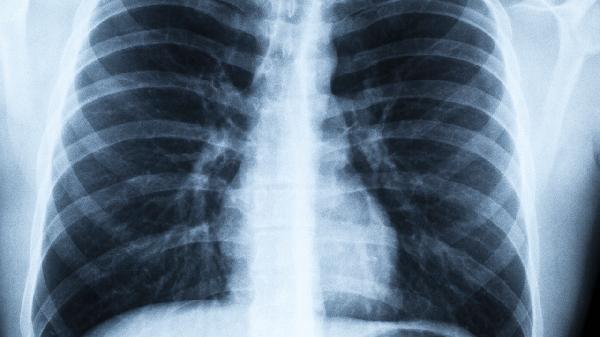

病毒性肺炎可通过抗病毒药物、对症支持治疗、免疫调节剂、中药制剂及并发症防治等方式治疗。病毒性肺炎通常由流感病毒、呼吸道合胞病毒、腺病毒、冠状病毒及副流感病毒等病原体感染引起。

合并细菌感染时需联用抗生素,出现急性呼吸窘迫综合征需采用肺保护性通气策略。糖皮质激素仅限用于特定重症病例,需警惕二重感染与血糖升高等不良反应。